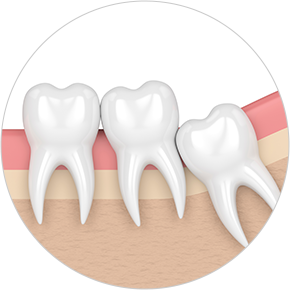

• Horizontally

impacted wisdom tooth